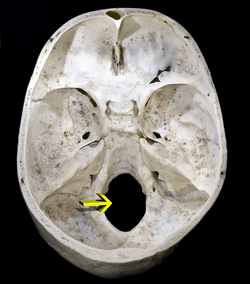

The foramen magnum (Latin: great hole) is a large oval opening (foramen) in the occipital bone of the skull in humans and various other animals. It is one of the several oval or circular openings (foramina) in the base of the skull. The spinal cord, an extension of the medulla, passes through the foramen magnum as it exits the cranial cavity. Apart from the transmission of the medulla oblongata and its membranes, the foramen magnum transmits the vertebral arteries, the anterior and posterior spinal arteries, the tectorial membranes and alar ligaments. It also transmits the spinal component of the accessory nerve into the skull.

The opisthion is the midpoint on the posterior margin of the foramen magnum and is a cephalometric landmark. Another landmark is the basion located at the midpoint on the anterior margin of the foramen magnum.

| Skull seen from below. The hole through which the medulla (shown in red) is passing is foramen magnum. |